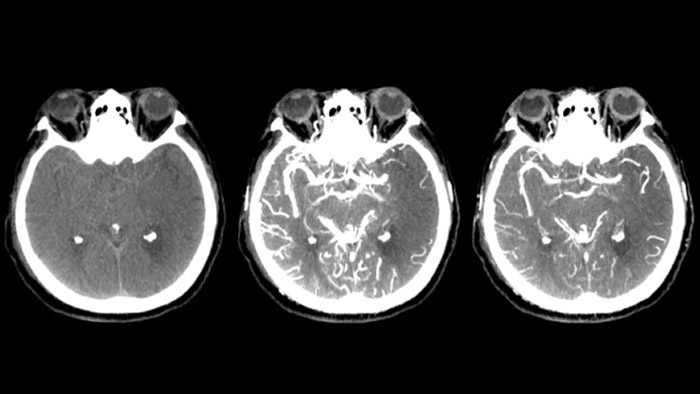

Tres SmartCT

Visualización similar a una TC

SmartCT Soft Tissue  genera una visualización de los tejidos blandos similar a la de una TC y apoya el diagnóstico del accidente cerebrovascular de tres maneras. Una exploración sin contraste ayuda a detectar los cambios isquémicos tempranos. Una exploración de fase temprana ayuda a identificar la oclusión proximal. Una exploración con contraste de fase tardía ayuda a detectar colaterales.

Ver llenado colateral

Visualización del llenado colateral

La vista dual para ver los volúmenes de TC de haz cónico de fase temprana y tardía uno al lado del otro mejora la identificación de las áreas de penumbra y permite la visualización del relleno colateral.